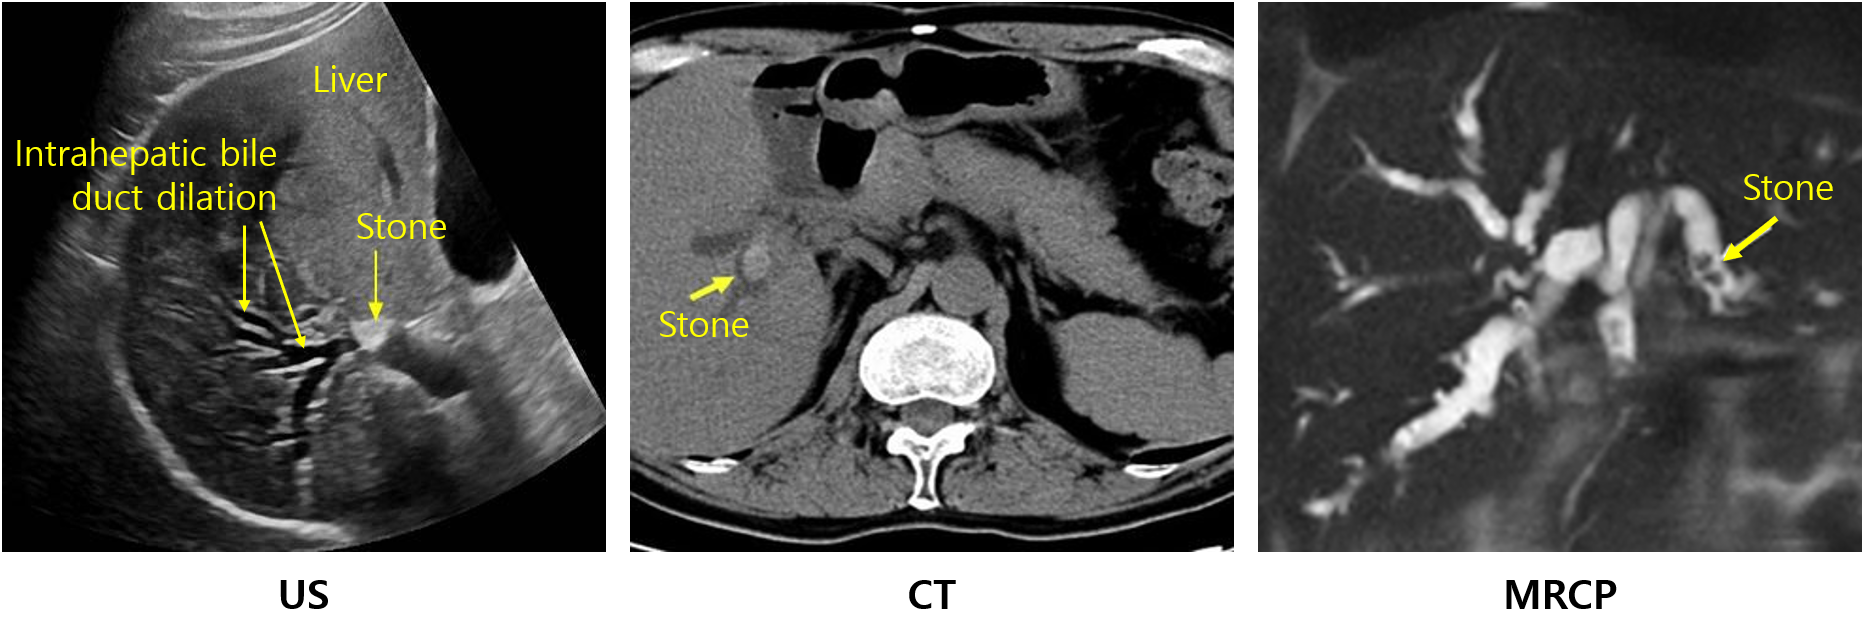

(1) 복부 US: 1차 검사로 시행할 수 있으나 distal CBD 및 췌장의 병리를 파악하는데 제한이 있을 수 있음

CBD stone, proximal bile duct dilatation(> 8mm), GB stone 유무 등 파악 가능

(2) 복부 CT: Distal CBD와 췌장을 잘 볼 수 있으며, 췌장염 합병 등 파악이 용이해서 동반 질환 평가가 필요한 경우 1차 검사로 적절함

(1) 복부 US: 간내 담관의 dilatation 확인

(2) CT, MRCP, ERCP, PTC: 간내 담석을 직접적으로 확인